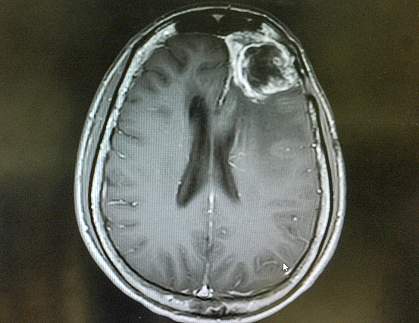

Hard-to-treat tumors known as gliomas originate in the brain or spinal cord. The subtype known as glioblastoma is the most common type of primary brain cancer in adults, and is especially aggressive. Affected patients usually have surgery to remove the tumor, followed by chemotherapy or radiation to eliminate any remaining cancer cells. Despite years of research, no biomarkers have been identified to help guide targeted treatment strategies. Unfortunately, survival rates for people with glioblastoma have not significantly improved over the past decades.

A research team led by Drs. Pierpaolo Peruzzi and Oliver Jonas of Brigham and Women’s Hospital developed and tested a novel approach for assessing how well various antitumor drugs might work for each patient. The scientists created tiny drug-releasing microdevices—each about the size of a grain of rice—that can be inserted into a patient’s tumor at the start of brain surgery. The device releases tiny “nano-doses” of anti-cancer drugs at separate locations within the tumor. The drugs then incubate in the patient’s tumor as the brain surgery proceeds for another two to three hours.